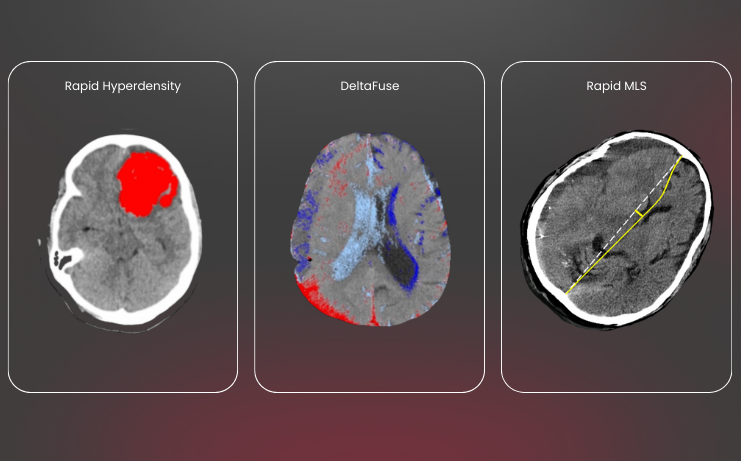

Holistic hemorrhage assessments

Don’t just detect suspected ICH and subdural hematomas, localize and quantify hyperdense tissue.

Rapid ICH: detection & measurement

Triage and hyperdensity– the dynamic duo for fast and accurate bleed assessment

Detect all acute hemorrhage types

Identify suspected intraparenchymal (IPH), intraventricular (IVH), subdural (SDH), and subarachnoid (SAH) hemorrhages

Quantify with confidence

Determine severity and volume of hematoma expansion with measurements down to 1 mL— supporting Joint Commission ICH score compliance